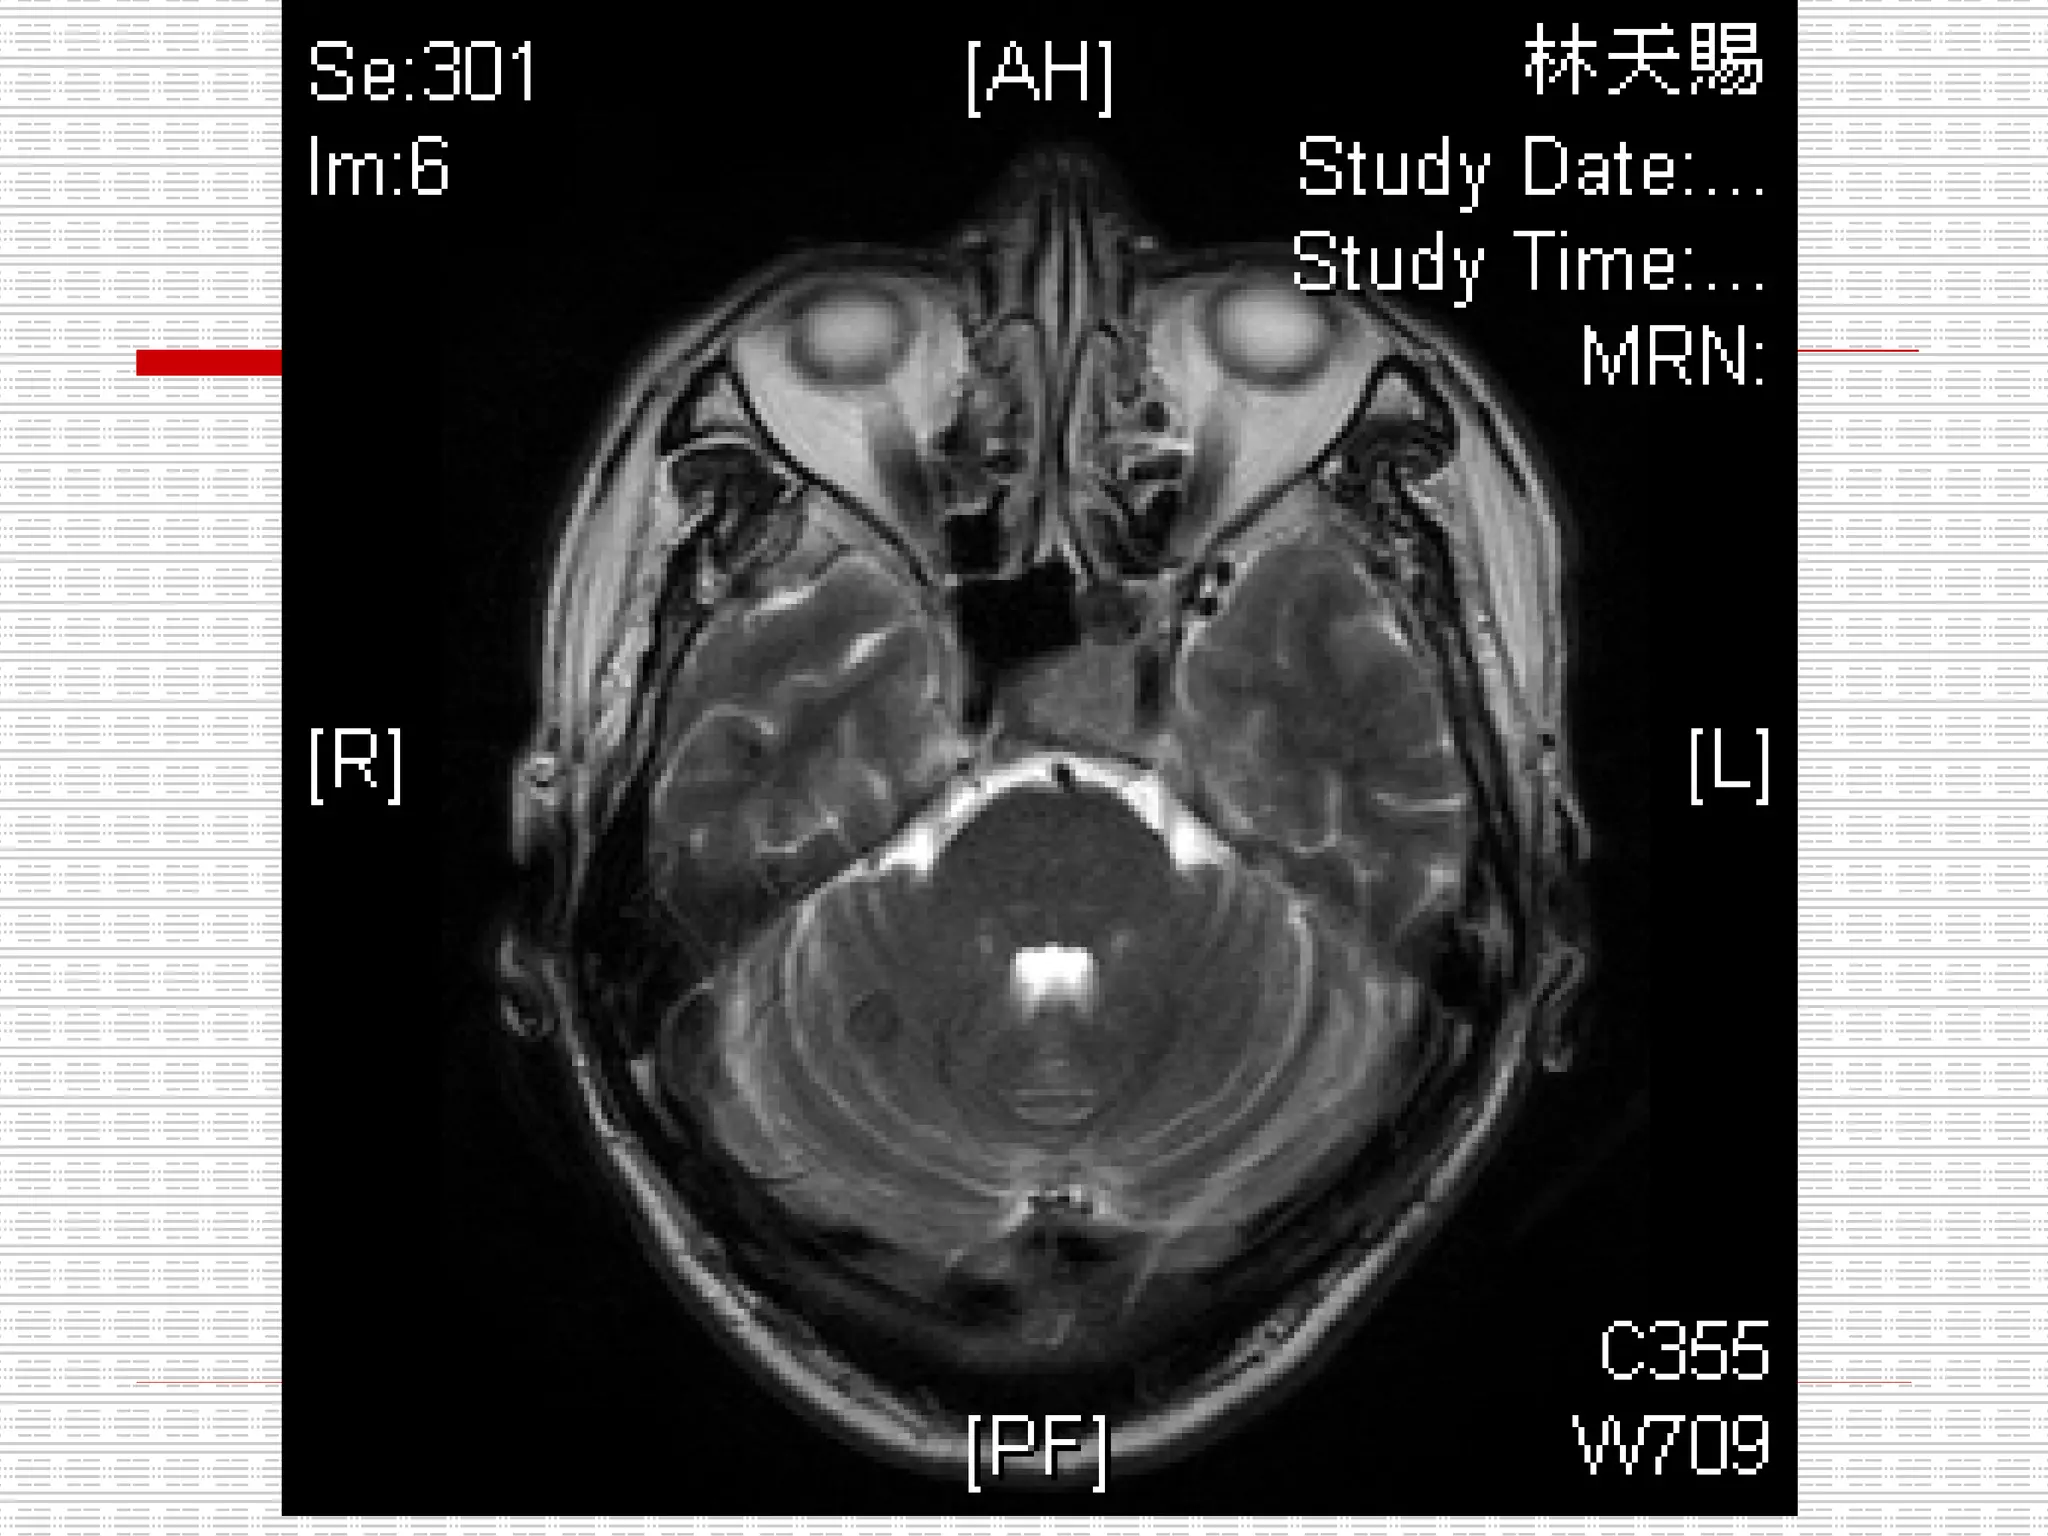

CT: Enlarged pituitary fossa with bony scalloping and soft tissue opacification

CT: Enlarged pituitaryfossa with bony scalloping and soft tissue opacification